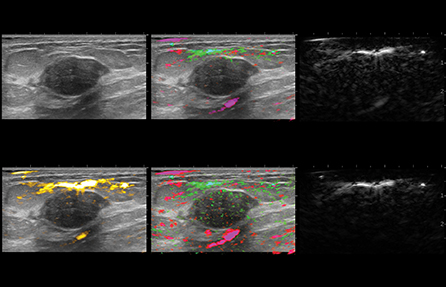

Signals from the sensors are analyzed and co-registered into images that present a real-time blood map of the lesion in easy to distinguish colors. OA image contrast is related to both blood volume and oxygenation status.

In general, malignant masses are more vascular and deplete oxygen from the blood at a higher rate than do benign masses. The two wavelengths of laser light used in the Imagio® system facilitate imaging by showing the relative differences between oxygenated and deoxygenated blood.